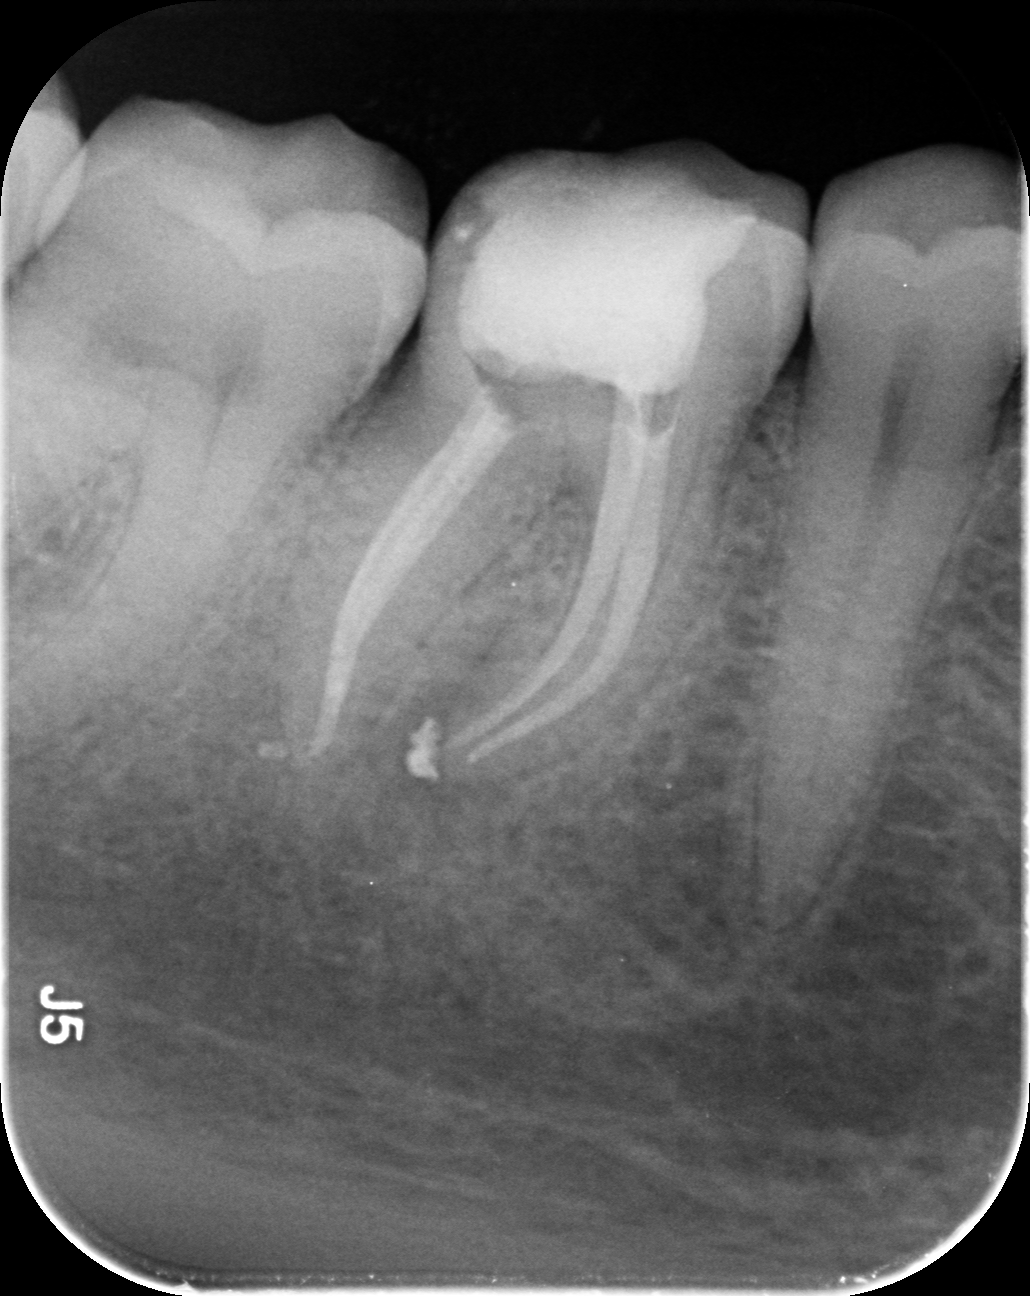

Dantų kanalų gydymas